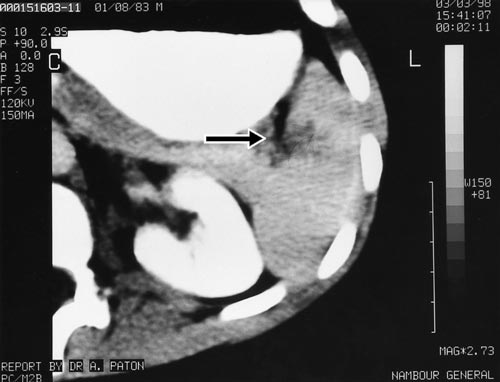

On presentation, six hours after the injury, he was pale and in pain. His pulse was 120/minute and blood pressure was 110/60 mmHg. He had marked tenderness in the left upper abdominal quadrant with guarding. A computed tomography (CT) scan of the abdomen revealed a full-thickness laceration of the spleen, extending into the hilum (Box 1).